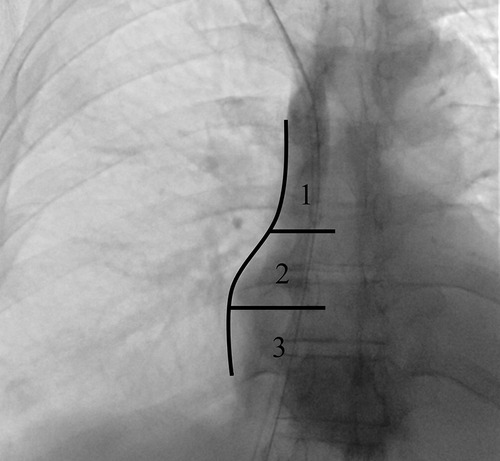

Background: Tunneled cuffed catheter (TCC) remains a crucial vascular access option for patients undergoing hemodialysis, particularly in those who are not candidates for arteriovenous fistulas or grafts. However, placement carries immediate and delayed complications. Objective: This narrative review aims to provide a comprehensive overview of the complications encountered during and after the placement of a TCC for hemodialysis, highlighting current evidence, risk factors, prevention strategies, and management approaches. Methods: A critical selection of relevant literature was performed through PubMed and Scopus databases, focusing on articles published in the last two decades. Particular attention was given to studies reporting on mechanical, infectious, thrombotic, and late-onset complications, as well as technical factors influencing outcomes. Results: Complications of TCCs can be classified as immediate (e.g., arterial puncture, pneumothorax, bleeding), early (e.g., catheter malposition, exit-site infections), and late (e.g., central venous stenosis, catheter-related bloodstream infections, thrombosis). Patient-and procedure-related factors increase risk. Ultrasound and fluoroscopy, strict sterility, and timely management reduce complications rates. Conclusion: TCCs are indispensable in selected patients, but understanding their complications is key to patient safety and outcomes. Optimal outcomes depend on accurate patient selection, operator expertise, and standardized post-placement care.